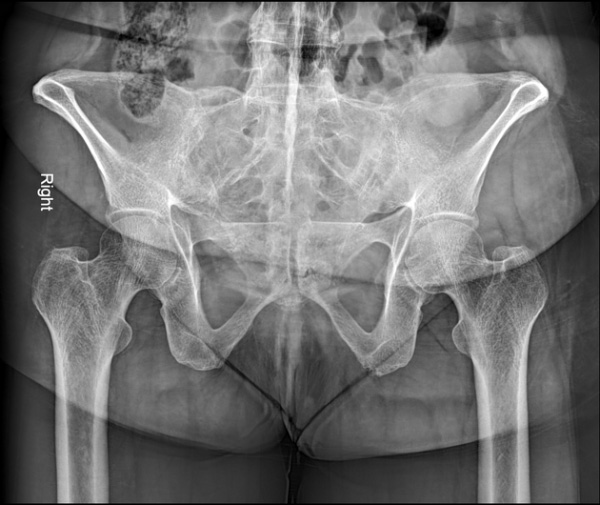

Chụp X-quang là phương pháp chẩn đoán hình ảnh viêm cột sống dính khớp được thực hiện đầu tiên giúp phát hiện các dấu hiệu viêm khớp cùng chậu, dính khớp cột sống và các thay đổi xương khác:

Hình ảnh X-quang viêm cột sống dính khớp có thể cho thấy các dấu hiệu như xói mòn xương, hình vuông hóa đốt sống, cầu xương (syndesmophytes) và dính khớp. Tuy nhiên, cần lưu ý rằng X-quang có độ nhạy hạn chế trong giai đoạn sớm của bệnh, khi các tổn thương viêm chưa gây ra thay đổi cấu trúc xương rõ ràng.

Sau đây là một số hình ảnh viêm cột sống dính khớp trên X-quang: